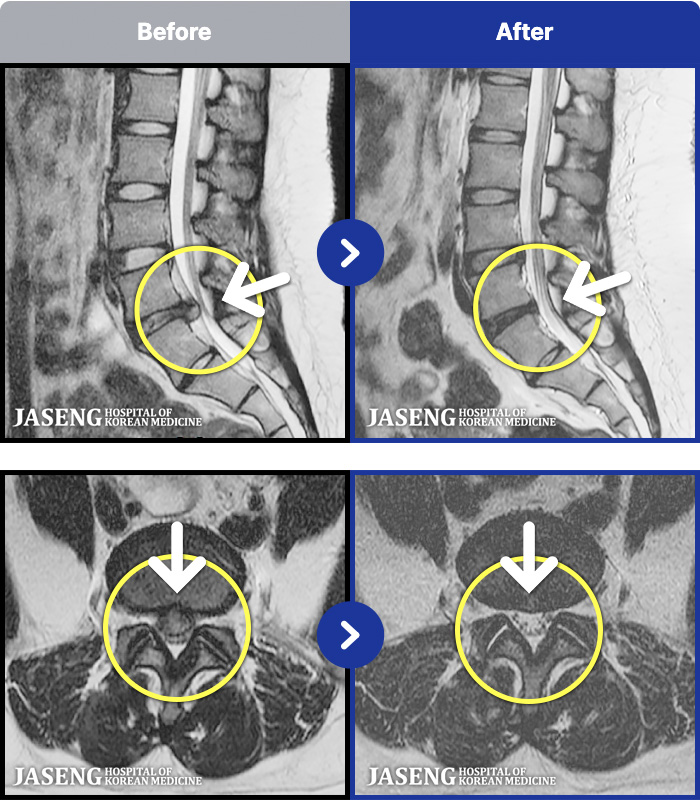

MRI ġ

1,301 MRI ũ ʸ Ȯϼ.

Ƹ ϰ ־.